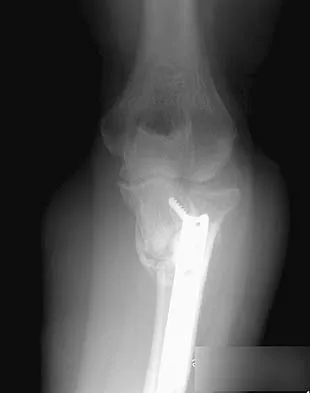

A 68-year-old woman who sustained a closed distal tibia fracture 2 years ago was initially treated with an external fixator across the ankle for 12 weeks, followed by intramedullary nailing of the fibula and lag screw fixation of the tibia. She continued to report persistent pain so she was treated with a brace and a bone stimulator. She now reports pain in her ankle. Examination reveals ankle range of motion of 8 degrees of dorsiflexion to 25 degrees of plantar flexion. She is neurovascularly intact. Current radiographs are shown in Figures 9a through 9c. What is the next most appropriate step in management?

Explanation